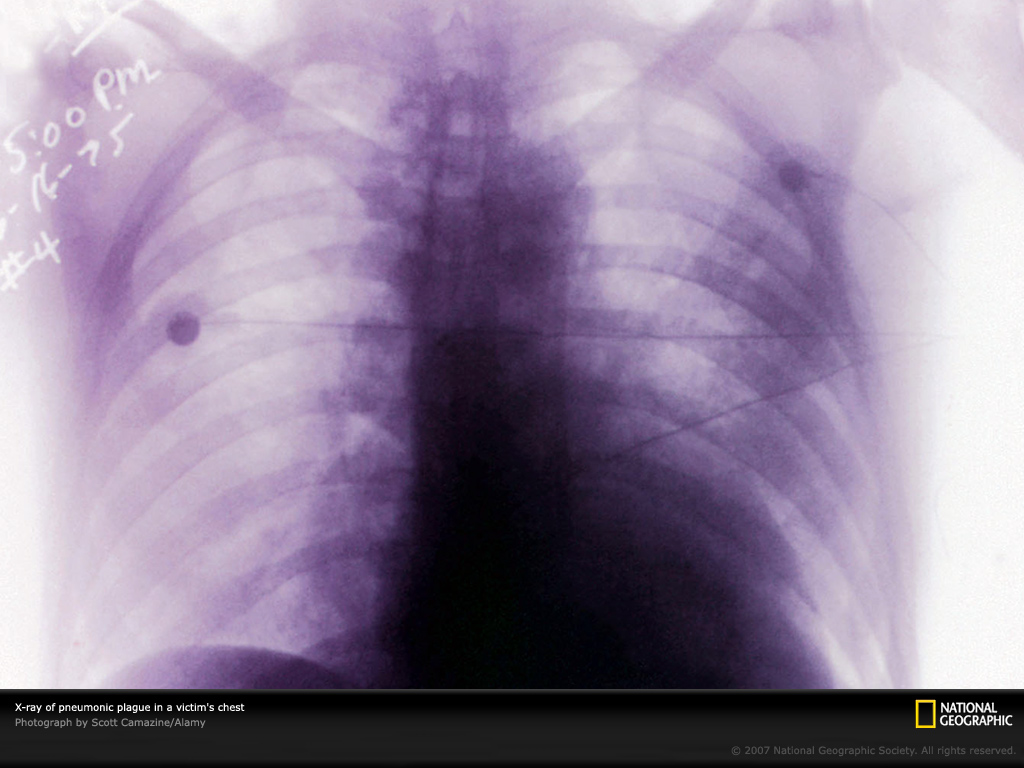

抗日战争时期,日本军国主义侵略我国,在东北研制、繁殖、各种渠道撒播鼠疫杆菌,用中国人做试验等令人发指,“国家地理杂志”在图片中作了介绍!。解放后,我国国内人间鼠疫已基本消灭,但自然疫源地依然存在,霸权主义者把鼠疫杆菌列为生物战剂之一,故防治鼠疫对我军国防和建设事业仍有非常重要意义。

下面请你观看11幅图片及说明词!Photo Gallery: Plague